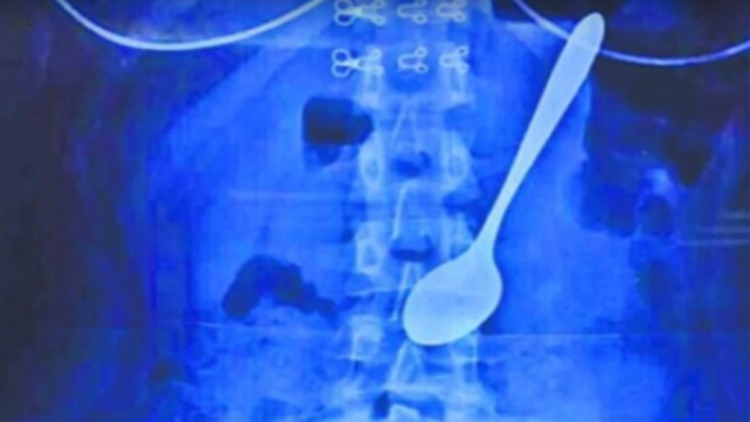

استطاع أطباء من مقاطعة "شينجيانغ" الصينية إنقاذ شاب كان قد ابتلع ملعقة طعام وعاش وهي بداخله عاما كاملا.

وذكر موقع ديلي ميل أن الشاب البالغ من العمر 26 عاما قدم إلى أحد مشافي المقاطعة مشتكيا من آلام في البطن وصعوبة في التنفس، وبعد معاينته، اكتشف الأطباء أن ملعقة طعام عالقة في المريء أسفل حلقه.

وبعد استجواب المريض، أخبر الأطباء أنه ومنذ نحو عام كان قد ابتلع الملعقة بالخطأ عندما كان في حالة سكر، وبقيت الملعقة بداخله طول تلك الفترة.

وقام الأطباء باستخراج الملعقة من داخل المريض عبر الفم، لكنهم ذكروا أنه سيخضع للعلاج بسبب الجروح والتقرحات التي أصابته في المريء.